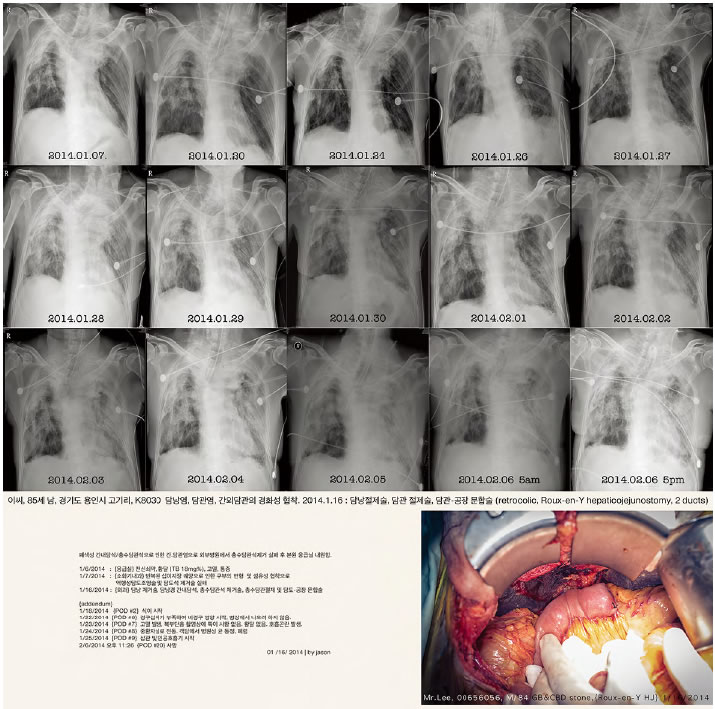

이 작업에 등장하는 환자들은 존재하며, 실제로 내가 만난 이들이다. 부디 그들의 신원과 영역을 존중해주시기를 바란다. 2005년 한 해 동안 국내에서만 7만 명이 ‘암’으로 사망하였다. 이런 비극적인 지표 이에서 연작